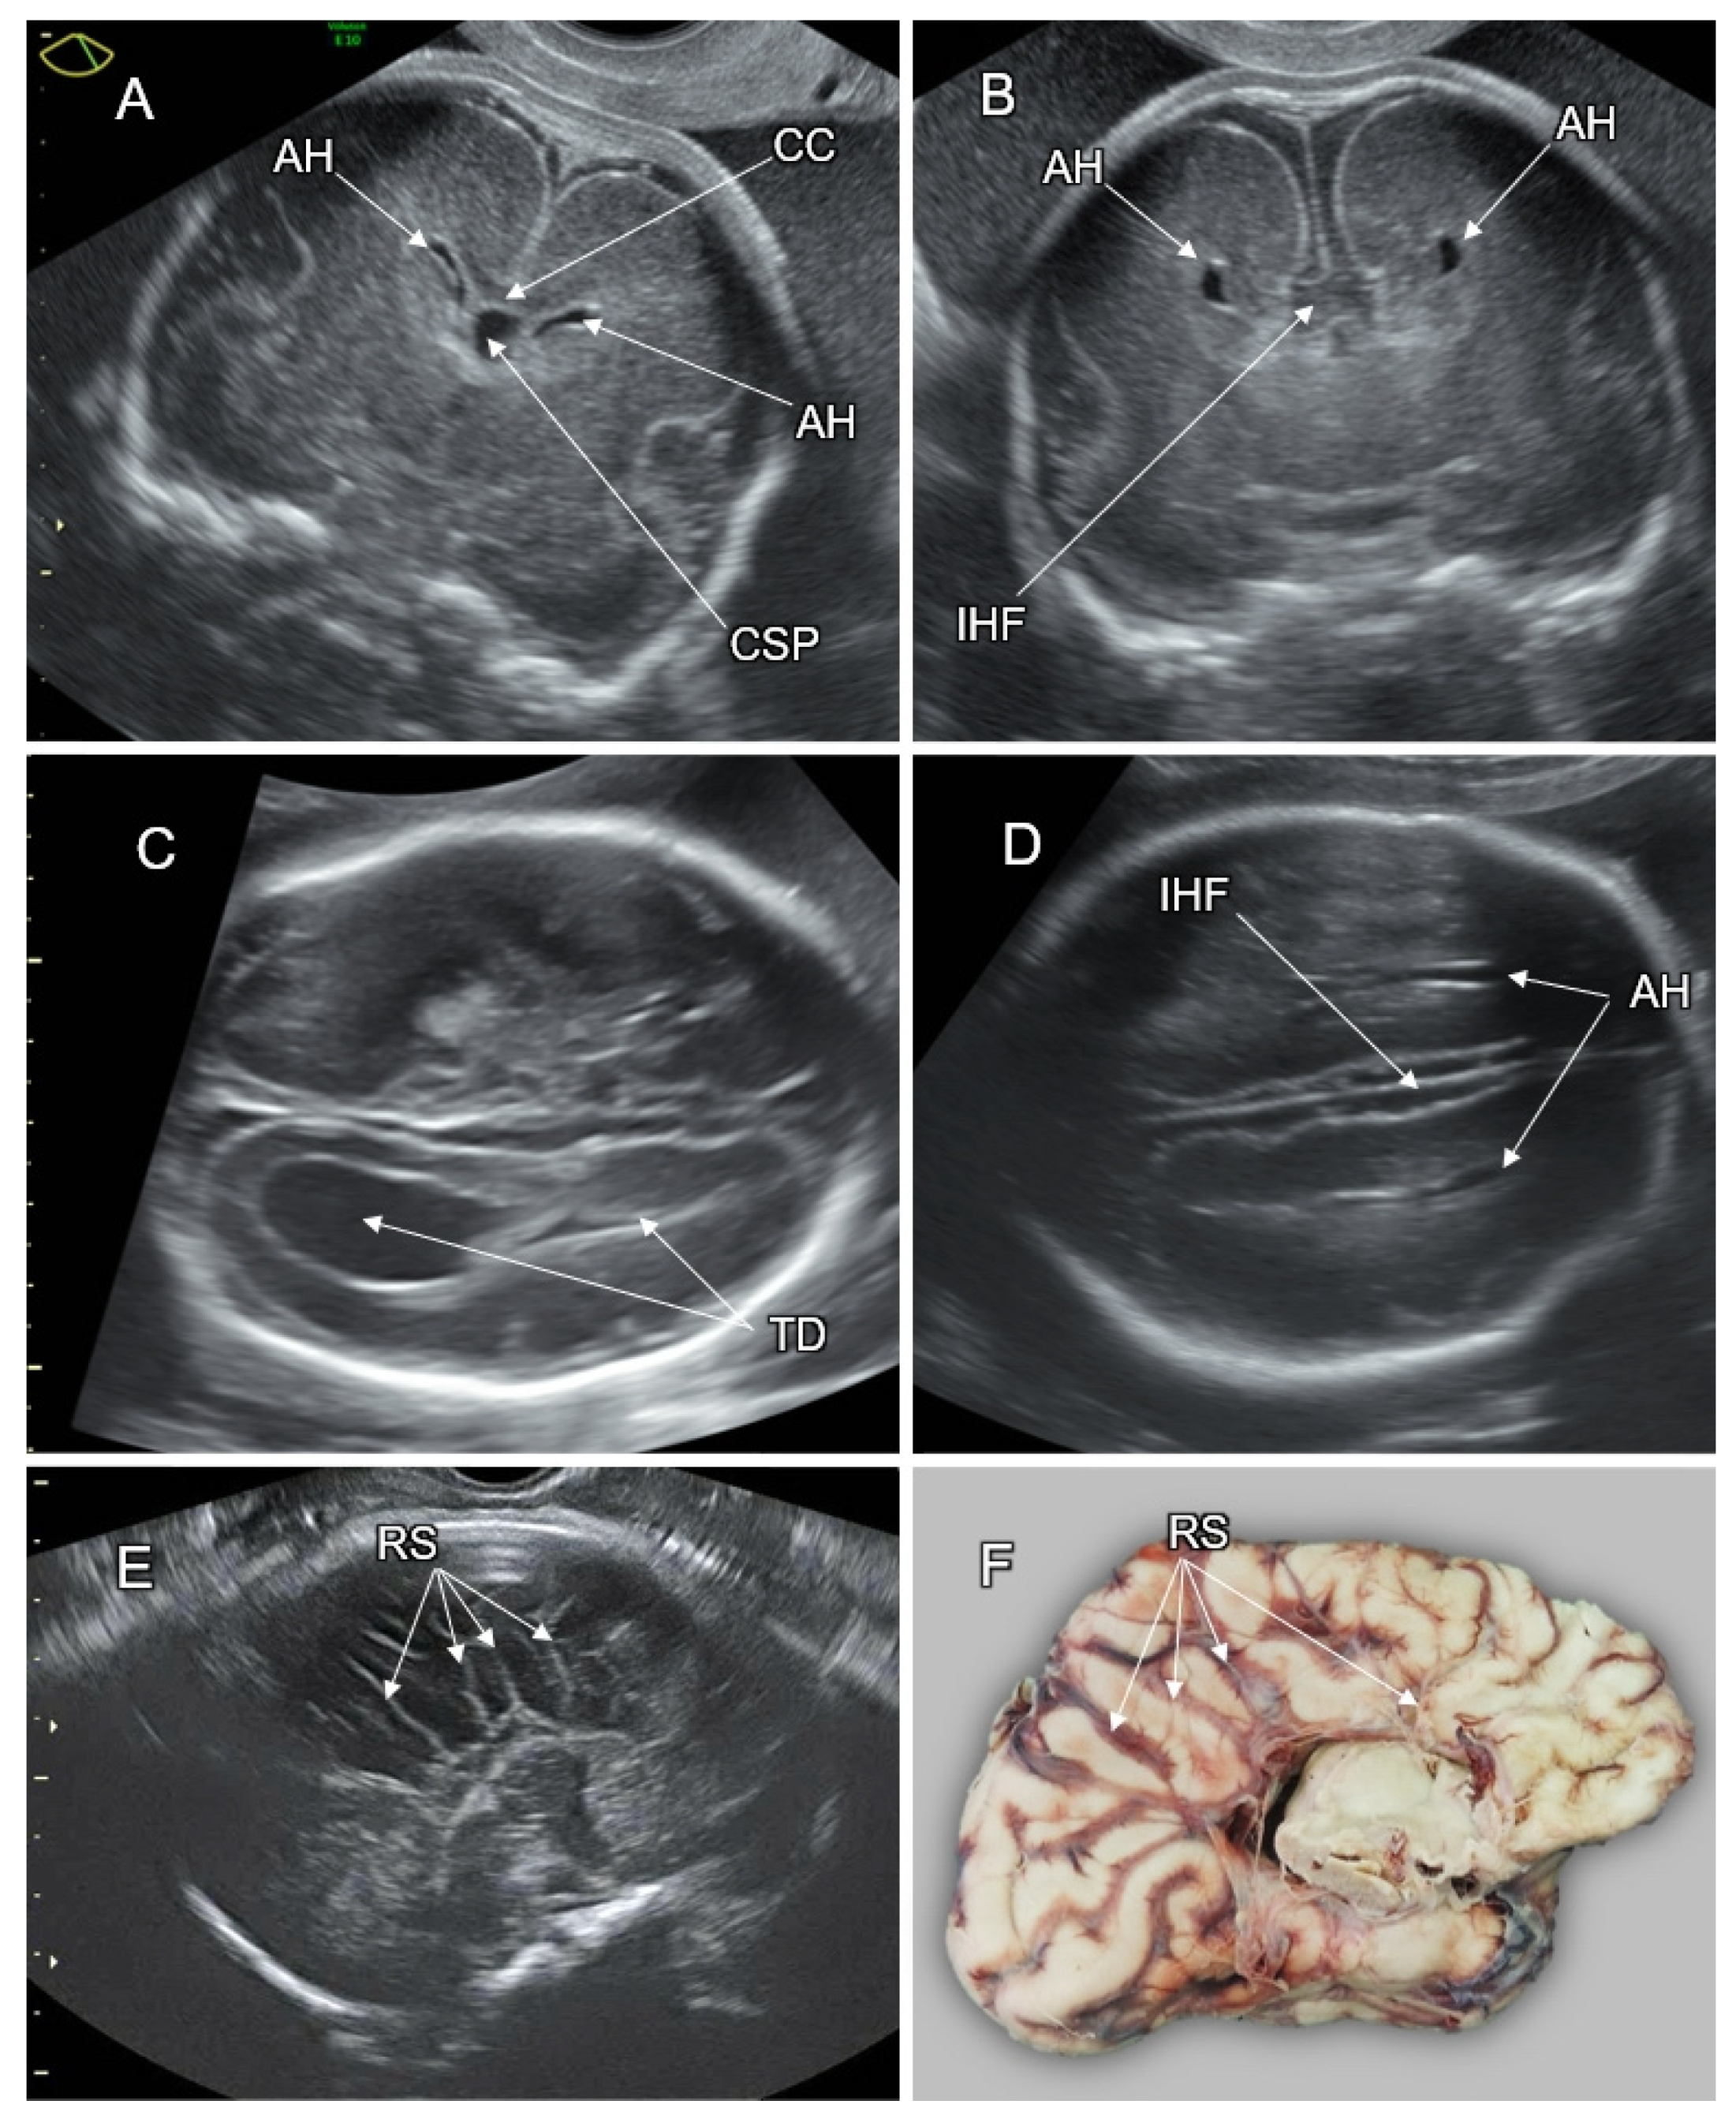

4.1. Alobar HPE

4.2. Semilobar HPE

4.3. Lobar HPE

4.4. Middle Interhemispheric Variant